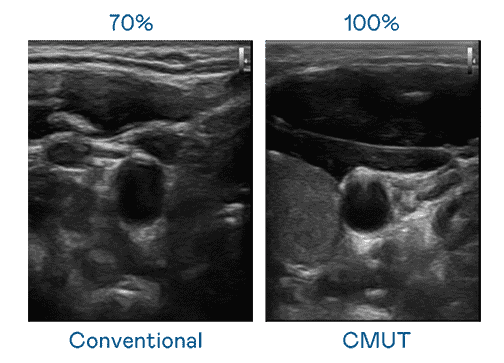

CMUT 技术是一种用电容式微机电元件来产生超音波讯号的技术。。。。与传统 PZT 压电式技术相比,,CMUT 频宽增加 30%,,,更宽频的超音波讯号让影像解析度大幅提升,,,是实现高影像品质医疗超音波扫描、、、、促进精准医疗发展的关键技术。。

超音波影像的解析度高低,,,,首先取决于探头能发出的讯号频宽。。NG大舞台 CMUT 可提供高清晰的超音波讯号,,,提供高频宽、、高灵敏度、、、影像纹理细节更高的超音波影像,,,协助医护人员缩短影像判读时间及利用精准的医疗影像进行诊断。。。。